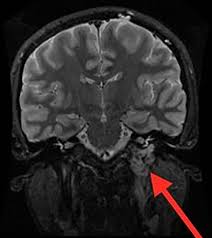

Pulsatile Tinnitus Ear Wax : The Radiology Assistant Pulsatile And Non Pulsatile Tinnitus / Removing the ear wax can provide relief from tinnitus.. Then, there is a probability that you are experiencing pulsatile tinnitus. Imaging and differential diagnosis. british tinnitus association: The sensation of hearing a rhythmic noise, such as a heartbeat, swooshing or whooshing, from no external source, is, at best, a little unsettling; Pulsatile (or vascular) tinnitus is a form of tinnitus and is usually heard in sync with the persons pulse. Pulsatile tinnitus is not tinnitus:

Unlike most types of tinnitus, it's caused by a physical source of sound. I get a lot of wax if you would like to learn how to cure your tinnitus permanently. Pulsatile (or vascular) tinnitus is a form of tinnitus and is usually heard in sync with the persons pulse. Pulsatile tinnitus is caused by blood circulating in or near your ears. It's also in my left ear but it's a very faint thump thump thump.

Pulsatile Tinnitus Recognise The Symptoms And Learn How To Manage from mk0hearingchoict79h1.kinstacdn.com Without drugs, without risky surgery, without any typical tinnitus treatments, and. Now getting dizzy during a water irrigation is common. It is caused by the sound of blood flowing through vessels. When there is an allergy or a sinus infection, the mucous thickens within the inner ear, and this causes more pressure. Tinnitus, hearing testing. national eye institute: If it is not wax, you need to get a hearing test. The latter is an incurable condition, the former is a symptom of an underlying condition which is some cases can be cured. The cause of pulsatile tinnitus is usually easier to find and as a result, this type of tinnitus can be more easily treated.

If it is not wax, you need to get a hearing test. Find out what causes it and how to treat it. The sound may be a ringing, whistling, or rushing sound, or it may be more complex like machinery or the twittering of birds. Tinnitus, hearing testing. national eye institute: The ringing or buzzing you hear with other kinds of tinnitus is a result of nerves picking up on abnormal electrical signals moving from your ears to your brain. A 2013 review of the current medical literature on pulsatile tinnitus indicated that It is caused by the sound of blood flowing through vessels. I get a lot of wax if you would like to learn how to cure your tinnitus permanently. Discussion in 'support' started by welsher, oct 25, 2014. Without drugs, without risky surgery, without any typical tinnitus treatments, and. Pulsatile tinnitus is a rare type of tinnitus that sounds like a rhythmic pulsing in the ear, usually in time with your heartbeat. This problem usually is related to blood flow, either through normal or abnormal blood vessels near the ear. Fast forward a month and i mention the earwax blockage/tinnitus in passing to my gp, so she looks inside my ears and says it's all clear, great;

Pulsatile tinnitus is a rare type of tinnitus that sounds like a rhythmic pulsing in the ear, usually in time with your heartbeat. If it is not wax, you need to get a hearing test. Pulsatile tinnitus is caused by a change in blood flow in the vessels that are located near the ear. The cause of pulsatile tinnitus is usually easier to find and as a result, this type of tinnitus can be more easily treated. Hydrogen peroxide is used to dissolve ear wax.

Pulsatile Tinnitus Symptoms Causes And Treatments from post.healthline.com Pulsatile tinnitus is caused by blood circulating in or near your ears. There are many causes, most are benign but still may a carotid ultrasound can test for carotid plaques which can cause pulsatile tinnitus and if obstructive or friable may cause a stroke. The latter is an incurable condition, the former is a symptom of an underlying condition which is some cases can be cured. The ear wax may be the root. Find out what causes it and how to treat it. The sensation of hearing a rhythmic noise, such as a heartbeat, swooshing or whooshing, from no external source, is, at best, a little unsettling; Like regular tinnitus, the pulsatile form of this condition has ringing in the ear as its chief symptom. A doctor may be able to what should i do if i have tinnitus?

Pulsatile tinnitus usually beats in cadence with the heart.